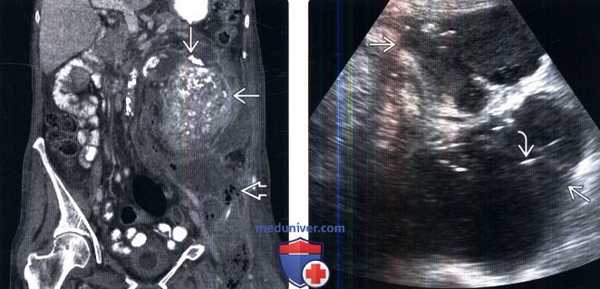

(Слева) КТ с контрастированием, аксиальная проекция: у мужчины 81 года с длительной болью в правом боку выявлена обструкция собирательной системы из-за крупного центрального конкремента в почечной лоханке. Обратите внимание на воспалительные изменения в околопочечном пространстве.

(Справа) КТ с контрастированием, аксиальная проекция: у этого же пациента выявлены воспалительные изменения в околопочечном пространстве и мелкие конкременты почки. Правая почка увеличена, ее форма сохранена.

(Слева) КТ с контрастированием, коронарная проекция: у пациента с подозрением на ксантогранулематозный пиелонефрит выявлена увеличенная и деформированная левая почка с множественными обтурирующими почечную лоханку конкрементами. Обратите внимание на крупный околопо-чечный абсцесс, распространяющийся на левую подвздошно-поясничную мышцу.

(Справа) УЗИ, поперечная плоскость сканирования: околопочечное гипоэхогенное скопление с внутренним высокочастотным эхо-сигналом, который представляет собой газ. Под ультразвуковым контролем введен дренаж. Анализ дренированной жидкости выявил Proteus mirabilis.